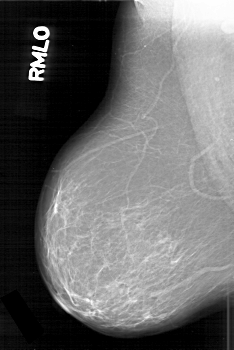

D_4195_1.RIGHT_MLO

RIGHT_CC LINES 6316 PIXELS_PER_LINE 4231 BITS_PER_PIXEL 12 RESOLUTION 43.5 NON_OVERLAY

RIGHT_MLO LINES 6286 PIXELS_PER_LINE 4201 BITS_PER_PIXEL 12 RESOLUTION 43.5 NON_OVERLAY